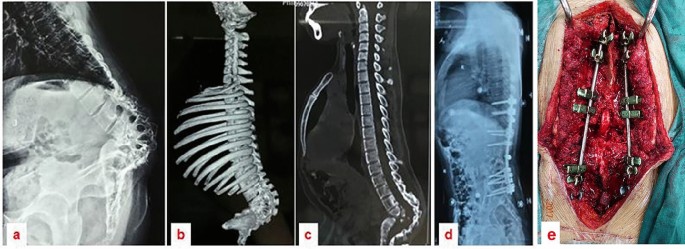

The surgical procedure averaged 492 ± 127.3 min in duration, with blood loss averaging 1791 ± 788.8 ml (range: 800–3000 ml). The follow-up period lasted 31.2 ± 5.49 months (range 24–42 months). The mean kyphotic angle experienced a substantial reduction postoperatively, descending from 97.6 ± 14.6° to 28.8 ± 18.70°, which constitutes a 65% correction rate. The lesions were localized to the lumbar spine in two patients, with a span from L1 to L5 in one case and from L2 to S1 in another. For the remaining patients, thoracic spinal lesions were identified. A three-column osteotomy was performed on the vertebra located below the apical region in 14 cases (Fig. 3), and above the apical region in two cases (Fig. 4). The respective preoperative kyphotic angles of these two patients were 85° and 61°, with postoperative lordosis angles recorded at 13° and 10°, respectively (Time scale analysis: − 13 and − 10). Post-surgical SVA readings indicated an improvement from 6.7 ± 3.58 to 3.3 ± 1.57 cm, effectively restoring the overall sagittal alignment of the spine, as detailed in Table 1. Neurological function was enhanced in six patients, whereas no substantial change was noted in the remaining ten at the final evaluation (Table 2).

27-year-old female patient with severe sharp angular kyphosis due to Pott’s disease. Image (a) shows a lateral radiograph of the entire spine. Images (b and c) display 3D CT scans of the spine, highlighting the sharp angular kyphosis affecting the lumbosacral region. Image (d) is a postoperative lateral radiograph in which satisfactory correction is evident subsequent to an osteotomy at T12. Image (e) exhibits an intraoperative view of the spinal cord at T12 following a three-column osteotomy.